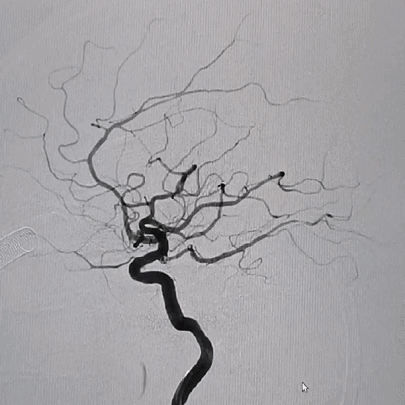

术前影像

栓塞过程

栓塞微导管精准塑形后,前推顺利到位,依次填塞三枚Jasper®SS弹簧圈。瘤颈处有壶腹,为增加弹簧圈稳定性,降低动脉瘤复发率,释放支架,复查造影,动脉瘤填塞致密,载瘤动脉通畅良好。

术后即刻影像

本例为大脑中动脉分叉处微小动脉瘤,和载瘤动脉M1具有明显的垂直成角现象,微导管顺利到位后,弹簧圈的成篮性不是重点,但对弹簧圈的柔软性和顺应性要求相对较高,Jasper®SS弹簧圈在术中展示出很好的柔软性和钻空能力,并且不易踢管,解脱快速,这都给手术顺利进行提供了很好的保障。